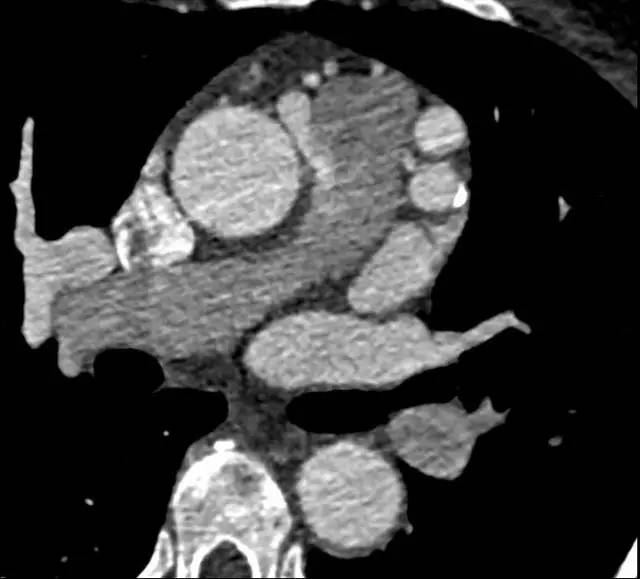

冠状动脉血管造影(CTA)回顾性心电门控扫描结果如下:

图 1

冠状动脉 CTA 是诊断该病理想的检查方法,轴位(图 1,2)及最大密度投影(图 3)CTA 显示右冠状动脉起源于主肺动脉。左冠状动脉主干显著代偿性扩张(图 4)。右冠状动脉未见狭窄及肌桥。左心室肥厚,左室射血分数为 55%。